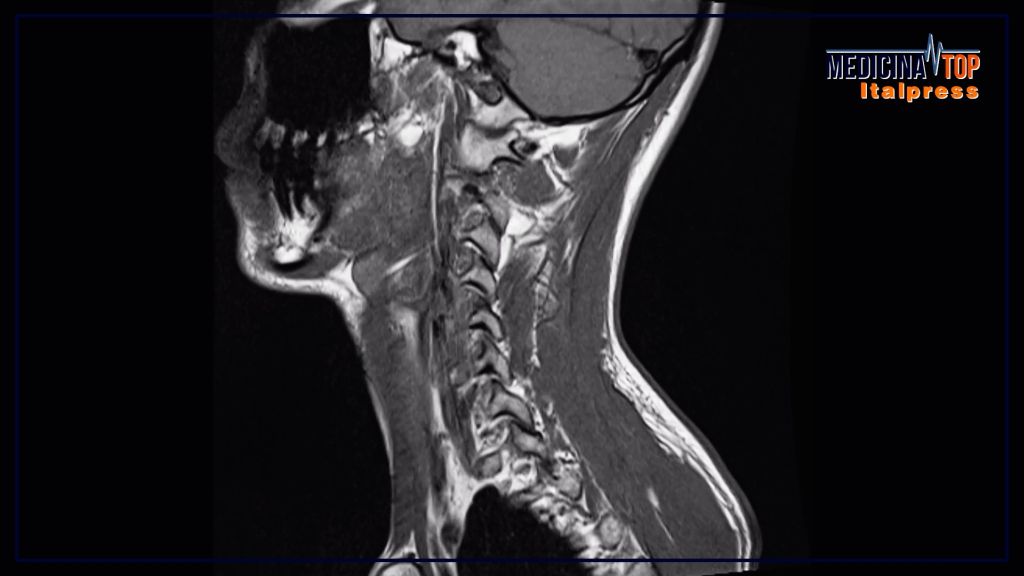

Negli ultimi anni si è osservato un aumento significativo dei casi di tumori all’orofaringe, che colpiscono la parte centrale della gola, inclusi tonsille e base della lingua. In Italia, si registrano oltre 6.000 nuovi casi all’anno, con un aumento particolarmente rilevante tra uomini di età compresa tra i 50 e i 70 anni, e tra i giovani adulti, a causa di stili di vita scorretti.

Il professor Giuseppe Mercante, esperto in Otorinolaringoiatria, sottolinea l’importanza di prestare attenzione ai segnali che potrebbero indicare un possibile tumore all’orofaringe, come tumefazioni del collo che non regrediscono, dolori lancinanti alla gola e sensazioni di corpo estraneo.

La diagnosi precoce riveste un ruolo fondamentale nella prognosi dei pazienti affetti da tumori all’orofaringe. Grazie ai continui progressi nelle cure e nei trattamenti chirurgici, la maggior parte dei casi ha una prognosi favorevole. È importante prestare attenzione ai segnali di un possibile tumore, come tumefazioni al collo, dolore persistente o difficoltà nella deglutizione. È essenziale poi sottoporsi a controlli medici regolari per individuare tempestivamente eventuali anomalie.